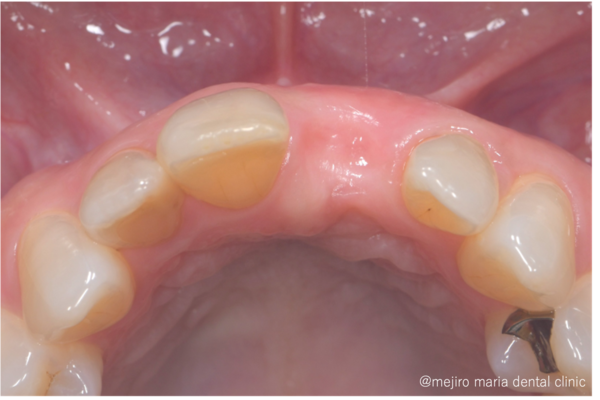

目白マリア歯科|歯周形成外科の症例|【症例】抜歯後の歯茎の凹みを低侵襲で予防し、接着性ブリッジを用いてインプラントを回避 歯槽堤保存術(Alveolar Ridge Preservation ; ARP) |凹み

治療後の様子

この症例では抜歯、歯槽堤保存術後4ヶ月ほど経ったところで補綴治療へと移行しました。

歯槽堤保存術を行ったことでほとんど歯茎は凹むことなく、自然な見た目で治療を終えることができました。